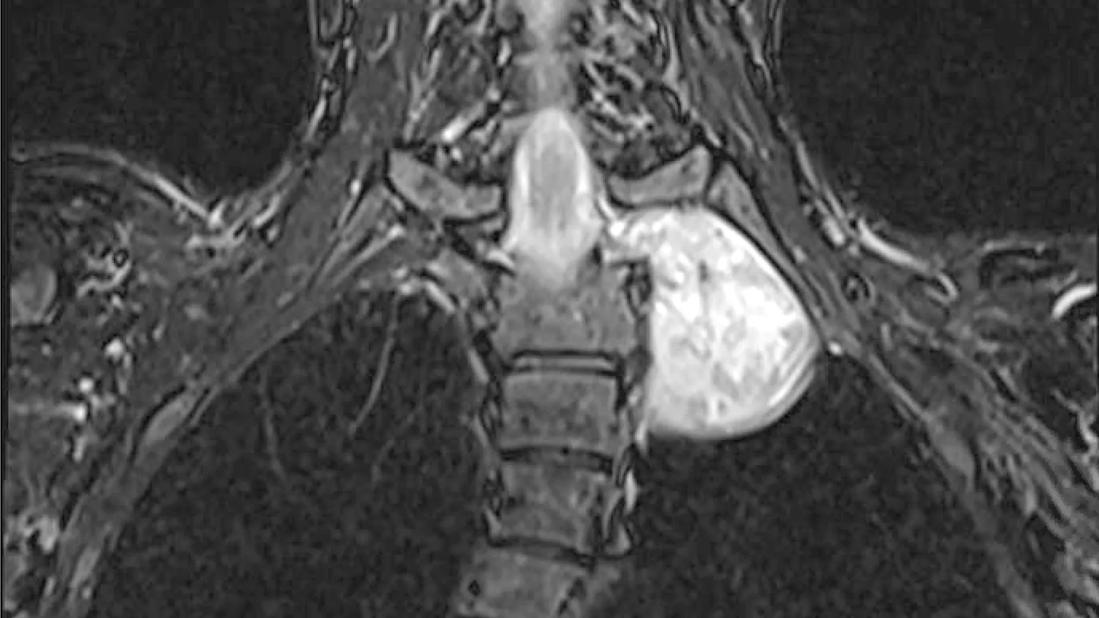

7 cm schwannoma at the intersection of the spine, lung and major arteries

Imaging depicting the 7 cm schwannoma in the superior mediastinum